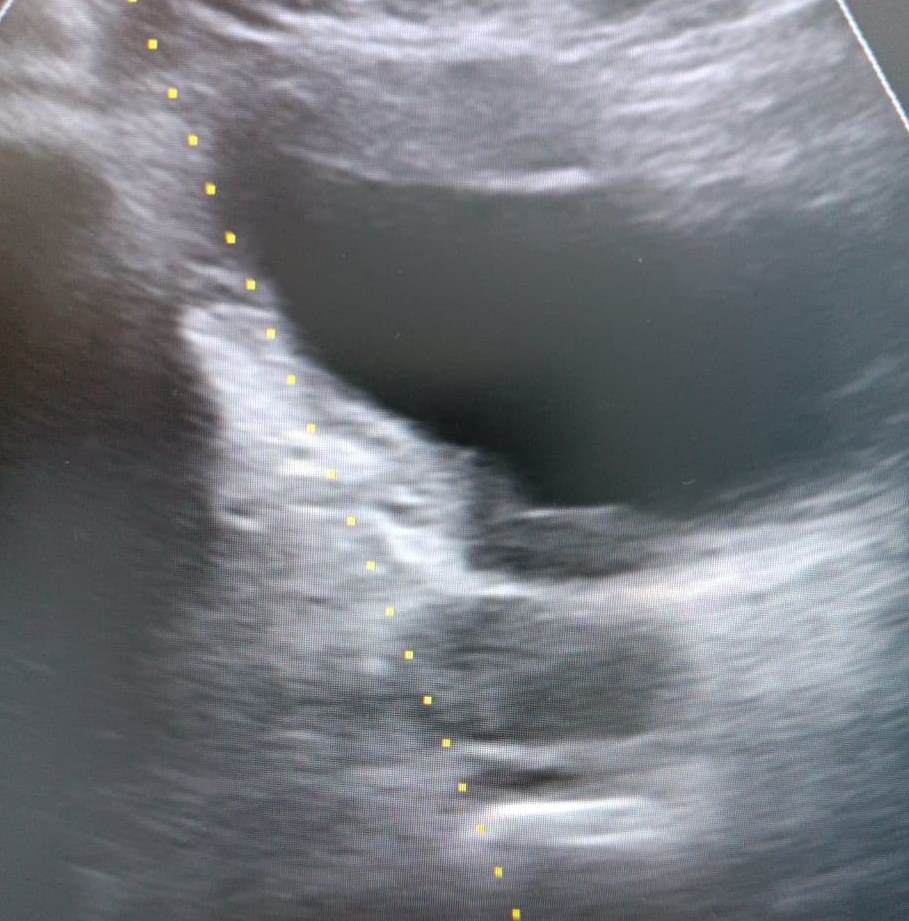

- УЗИ предстательной железы (чаще выполняется через задний проход с использованием высокочастотной аппаратуры) – изучают размеры простаты и мочевого пузыря, проводится оценка степени тяжести и распространенности воспалительных процессов на органы малого таза